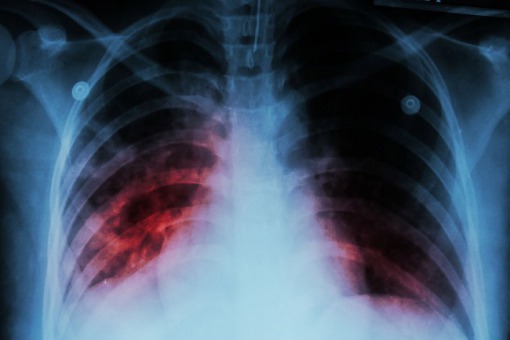

W Kazachstanie zaobserwowano przypadki ciężkiego zapalenia płuc o wysokiej śmiertelności

Ambasada chińska w Kazachstanie przestrzega swoich obywateli przebywających w tym kraju przed szerzącym się tam zapaleniem płuc o niewyjaśnionej etiologii i znacznie wyższej śmiertelności niż COVID-19. Problem nie został jeszcze jednoznacznie zidentyfikowany. Trwają badania nad przyczyną choroby.

- Kazachstańskie ministerstwo zdrowia i inne organizacje prowadzą badania porównawcze nad wirusem tego zapalenia płuc z wywoływanym przez SARS-CoV-2. Problem nie został jeszcze jednoznacznie zidentyfikowany - napisano w komunikacie opublikowanym na stronie internetowej ambasady chińskiej.